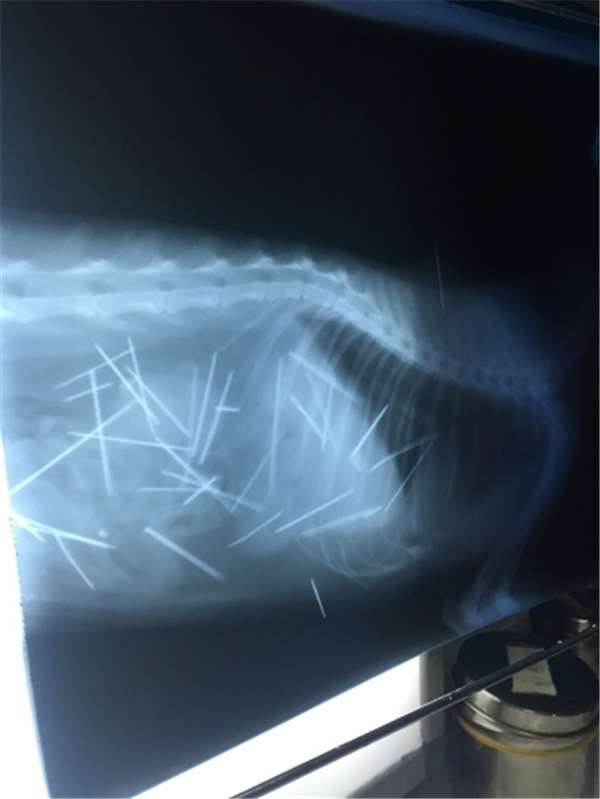

不去拍个片,很多铲屎官根本猜不到猫咪会吃下去什么。小玻璃球、发绳、毛线、咬碎的塑料壳等等,这还都不是最恐怖的,恐怖的是很多猫会吞针,有的猫还吞好几根针。

这些东西进入猫咪肠胃后当然会刺激肠胃,导致猫咪呕吐。有些时候比较幸运,猫咪能自行催吐出来。如果猫咪一直呕吐却吐不出来,或者连续几天都有呕吐,那一定要带猫咪去医院,看猫咪是不是吞了什么东西了。